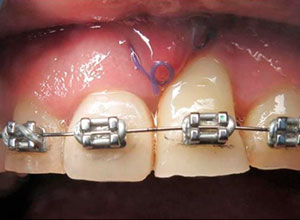

Al término de la distracción dejamos pasar tres meses con una férula en acrílico. En el diente 21 que habíamos visto en la radiografía un problema de un absceso periapical y periodontal.

Sutura y reconstrucción del tejido blando papilar

Dejamos que el implante se oseointegre para terminar con la rehabilitación protésica.

Nótese la colocación de los postes y el respeto a la forma de los tejidos gingivales y las papilas, muy importante para obtener el resultado estético final.